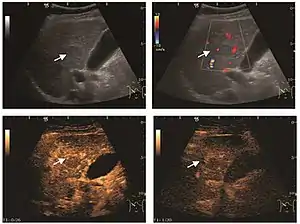

Liver metastases

US examination is required to detect liver metastases in patients with oncologic history. In addition, the method can incidentally detect metastases in asymptomatic patients. Early identification (small sizes, small number) is important to establish an optimal course of treatment which can be complex (chemotherapy, radiofrequency ablation, surgical resection) but welcomed. In addition, discrimination of synchronous lesions that have a different nature is also important knowing that up to 25–50% of liver lesions less than 2 cm detected in cancer patients may be benign . US sensitivity for metastases detection varies depending on the examiner's experience and the equipment used and ranges between 40–80% . Sensitivity is conditioned by the size and acoustic impedance of the nodules. For a lesion diameter below 10 mm US accuracy is greatly reduced, reaching approx. 20%. Other elements contributing to lower US performance are: excessive obesity, fatty liver disease, hypomobility of the diaphragm, and certain patterns of hyperechoic or isoechoic metastases that can be overlooked or can mimic benign conditions. Conventional US appearance of metastases is uncharacteristic, consisting of circumscribed lesions, with clear, imprecise or "halo" delineation, with homogeneous or heterogeneous echo pattern. They can be single (often liver metastases from colonic neoplasm) or multiple. Echogenity is variable. When increased, they can compress the bile ducts (which may be dilated) and the liver vessels. Liver involvement can be segmental, lobar or generalized. In this situation a pronounced hepatomegaly occurs. Generally, metastases have non-characteristic Doppler vascular pattern, with few exceptions (carcinoid metastases). Cyst-adenocarcinoma metastases due to semifluid content may have a transonic appearance. When increasing, they can result in central necrosis. CEUS examination is a real breakthrough for detection and characterization of liver metastases.

Increased performance is based on identifying specific vascular patterns during the arterial phase and seeing metastases in contrast to normal liver parenchyma during the sinusoidal phase. CEUS increased accuracy is due to the different behavior of normal liver parenchyma (captures CA in Kuppfer cells) against tumor parenchyma (does not contain Kuppfer cells, therefore CEUS appearance is hypoechoic). To this adds the particularities of intratumoral circulation represented by a reduced arterial bed compared to that of the surrounding normal liver and the absence of the portal vessels . In terms of vascularity, metastases can be hypovascular (in gastric, colonic, pancreatic or ovarian adenocarcinomas) with hypoechoic pattern during arterial phase, and similar during portal venous and late phases, respectively hypervascular (neuroendocrine tumors, malignant melanoma, sarcomas, renal, breast or thyroid tumors) with hyperechoic appearance during arterial phase, with washout during the portal venous phase and hypoechoic pattern 30 seconds after injection.